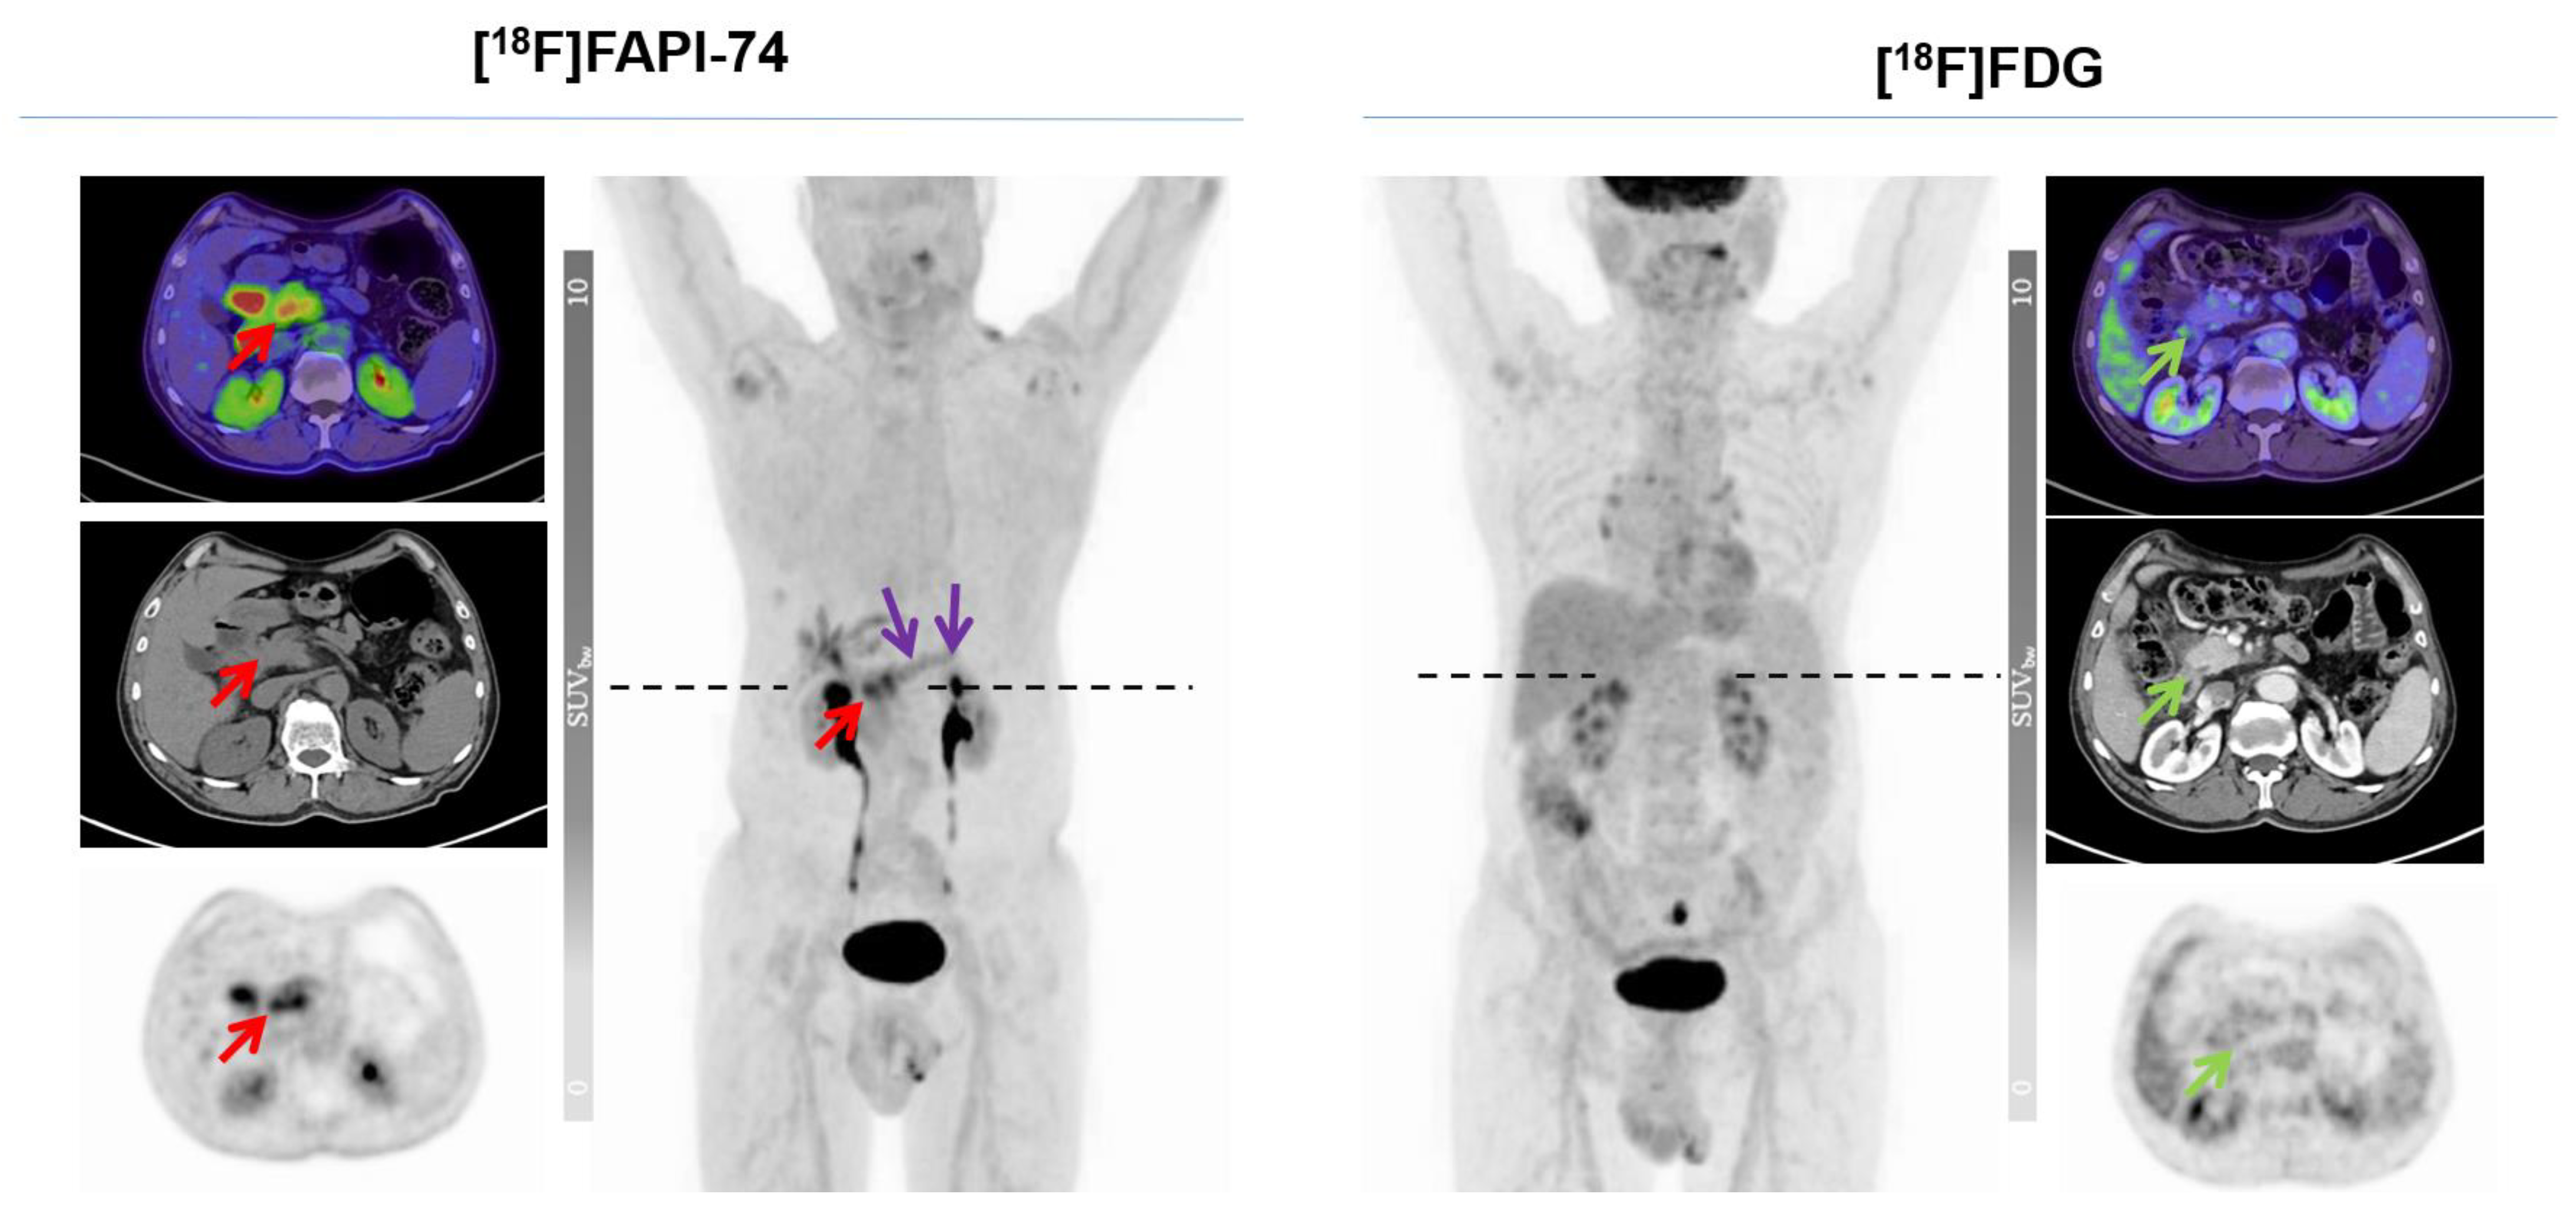

Head-to-Head Intra-Individual Comparison of Biodistribution and Tumor Uptake of [18F]FAPI-74 with [18F]FDG in Patients with PDAC: A Prospective Exploratory Study

Novruzov, E.; Giesel, F.L.; Mori, Y.; Choyke, P.L.; Dabir, M.; Mamlins, E.; Schmitt, D.; Antke, C.; Pinto, C.; Soza-Ried, C.; et al. Head-to-Head Intra-Individual Comparison of Biodistribution and Tumor Uptake of [18F]FAPI-74 with [18F]FDG in Patients with PDAC: A Prospective Exploratory Study. Cancers 2023, 15, 2798. https://doi.org/10.3390/cancers15102798